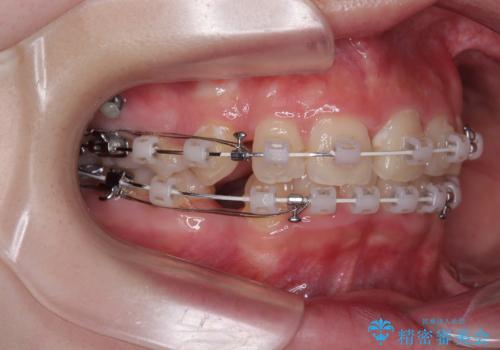

【モニター】デコボコと隠れてしまう前歯 ワイヤー装置による抜歯矯正で美しい口元に

- 審美装置

- デコボコになっている前歯を気にして来院された患者様です。

口元の突出感は気になっていないものの、デコボコを解消すると口元が前方に突出する可能性があるため、上下左右の第一小臼歯4本を抜歯して、ワイヤー装置にて矯正治療を行うこととしました。

下の前歯が隠れてしまうほど深く咬みこんでいたため、上顎前歯が前方に突出しているような印象がありましたが、咬み合わせが改善され、整った口元に仕上げることができました。